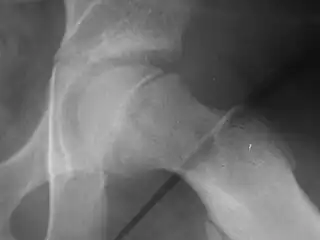

Slipped capital femoral epiphysis before surgery

Xray showing SCFE